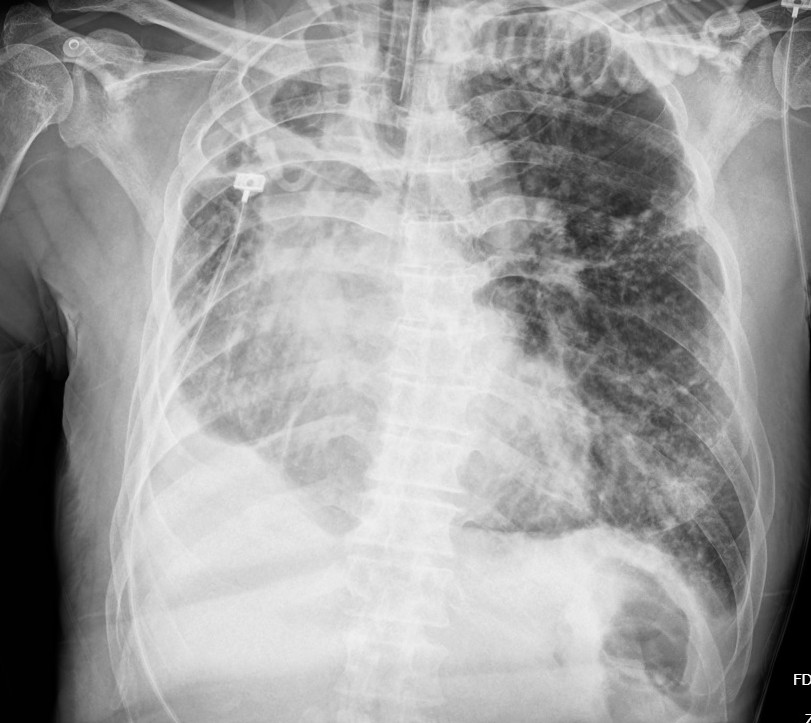

The initial electrocardiogram showed a sinus rhythm rate of 66 beat per minute with new T wave inversion in V2 to V6 and I, aVL. The Chest Xray showed increase CT ratio with pulmonary congestion with visualized endotracheal tube and no significant change of destroyed right lung. The transthoracic echocardiography demonstrated a left ventricular ejection fraction of 33% with anterior and lateral wall hypokinesia from basal to apex and no significant valvular abnormalities.